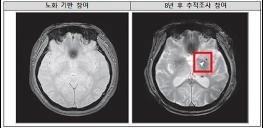

질병관리청 국립보건연구원은 ‘뇌질환 연구기반 조성 연구사업(BRIDGE)’을 통해 수행한 연구 결과, 파킨슨병 환자에서 시각-공간 인지능력이 다른 인지 영역보다 먼저 감소하는 경우 치매로 진행될 위험이 가장 높다는 사실을 확인했다.

파킨슨병, 공간 인지능력 빨리 떨어질수록 치매 전환 위험 커져

질병관리청 국립보건연구원은 ‘뇌질환 ..